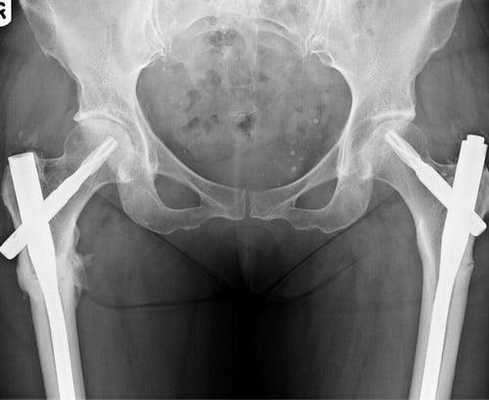

Остеосинтез ТБС на рентгене